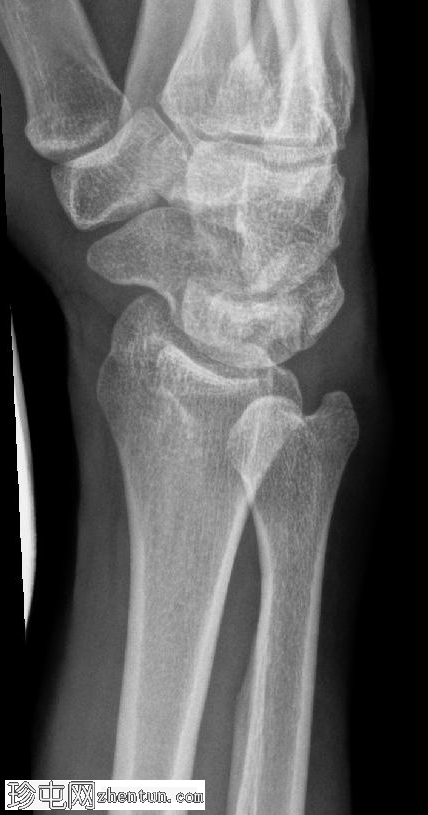

X线片

侧位片

可见豌豆骨皮质明显中断,并伴有一小块邻近骨碎片,符合皮质骨折的表现。此外,其上方软组织肿胀,提示急性骨折。

尺骨茎突可见透亮区,符合无移位尺骨茎突骨折的表现。